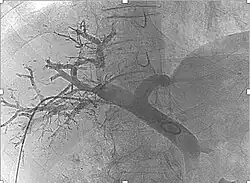

Para realizarlo se accede mediante cateterismo al vaso sanguíneo que lleva sangre al tumor y se administran microesferas que contienen el radioisótopo Itrio I-90, el cual emite partículas beta. De esta forma se consiguen dos objetivos, por un lado se restringe la llegada de sangre a las células tumorales (embolización), y por otro se administra una dosis de radiación a los tejidos malignos sin afectar al tejido sano.